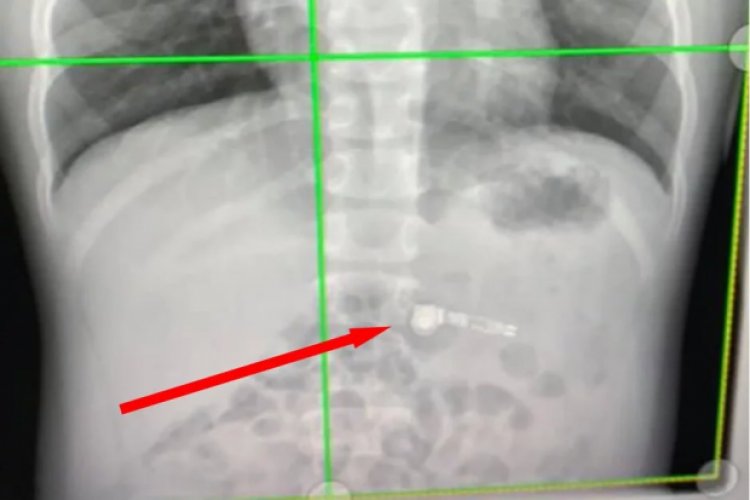

Як розповіла Кіара, хлопчик просто тримав один навушник у роті за довгу частину, а потім проковтнув, вона навіть не встигла відреагувати. Коли вона звернулась по допомогу до медиків, то фахівці в відділі охорони здоров'я дітей Атланти були спантеличені. Розміщення AirPod виявили вже на рентгенівському знімку.

Та операцію проводити не довелось, медики вирішили, що AirPod вийде природним чином. До речі, через цей інцидент хлопчик навіть відмовився торкатися до свого новенького iPhone.